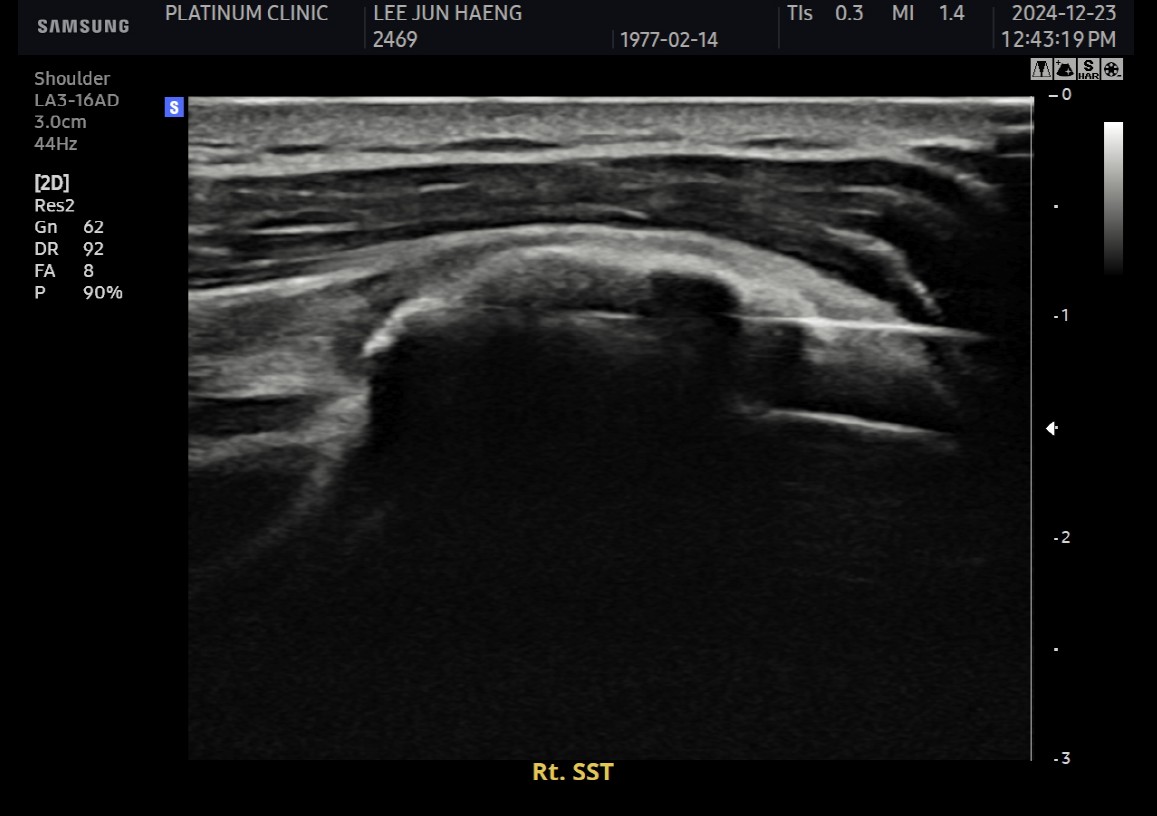

진단:

X-ray: 약 1.3cm 석회 (휴지기)

초음파: 석회 주변 인대 염증 소견